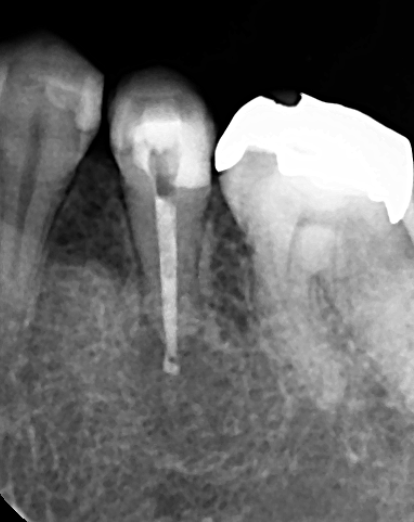

精密根管治療を行った根管充填時のレントゲン写真です。根の先までしっかり根管充填しました。